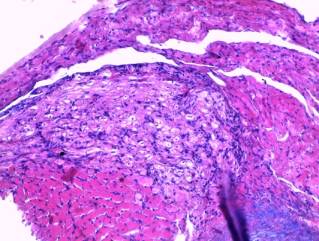

-

trabecular liver structure on cuts from different liver lobes doesn’t

detect violations. Hepatocytes’ borders are clear, cytoplasm is granular. There

are no local tinctorial properties disorders of cytoplasm. Nuclea contain clear

nucleola and sufficient quantity of chromatin. Nuclear membrane is thin.

Liver’s sinusoids are plethoric (picture 2);

Picture 2

Histological research

results

(liver’s sinusoids

plethora)